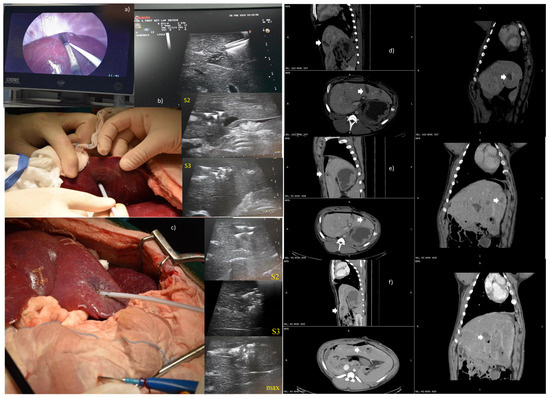

2.3.1. Liver Intervention in Laparoscopy or Laparotomy Approach

2.4. Imaging Data Analysis